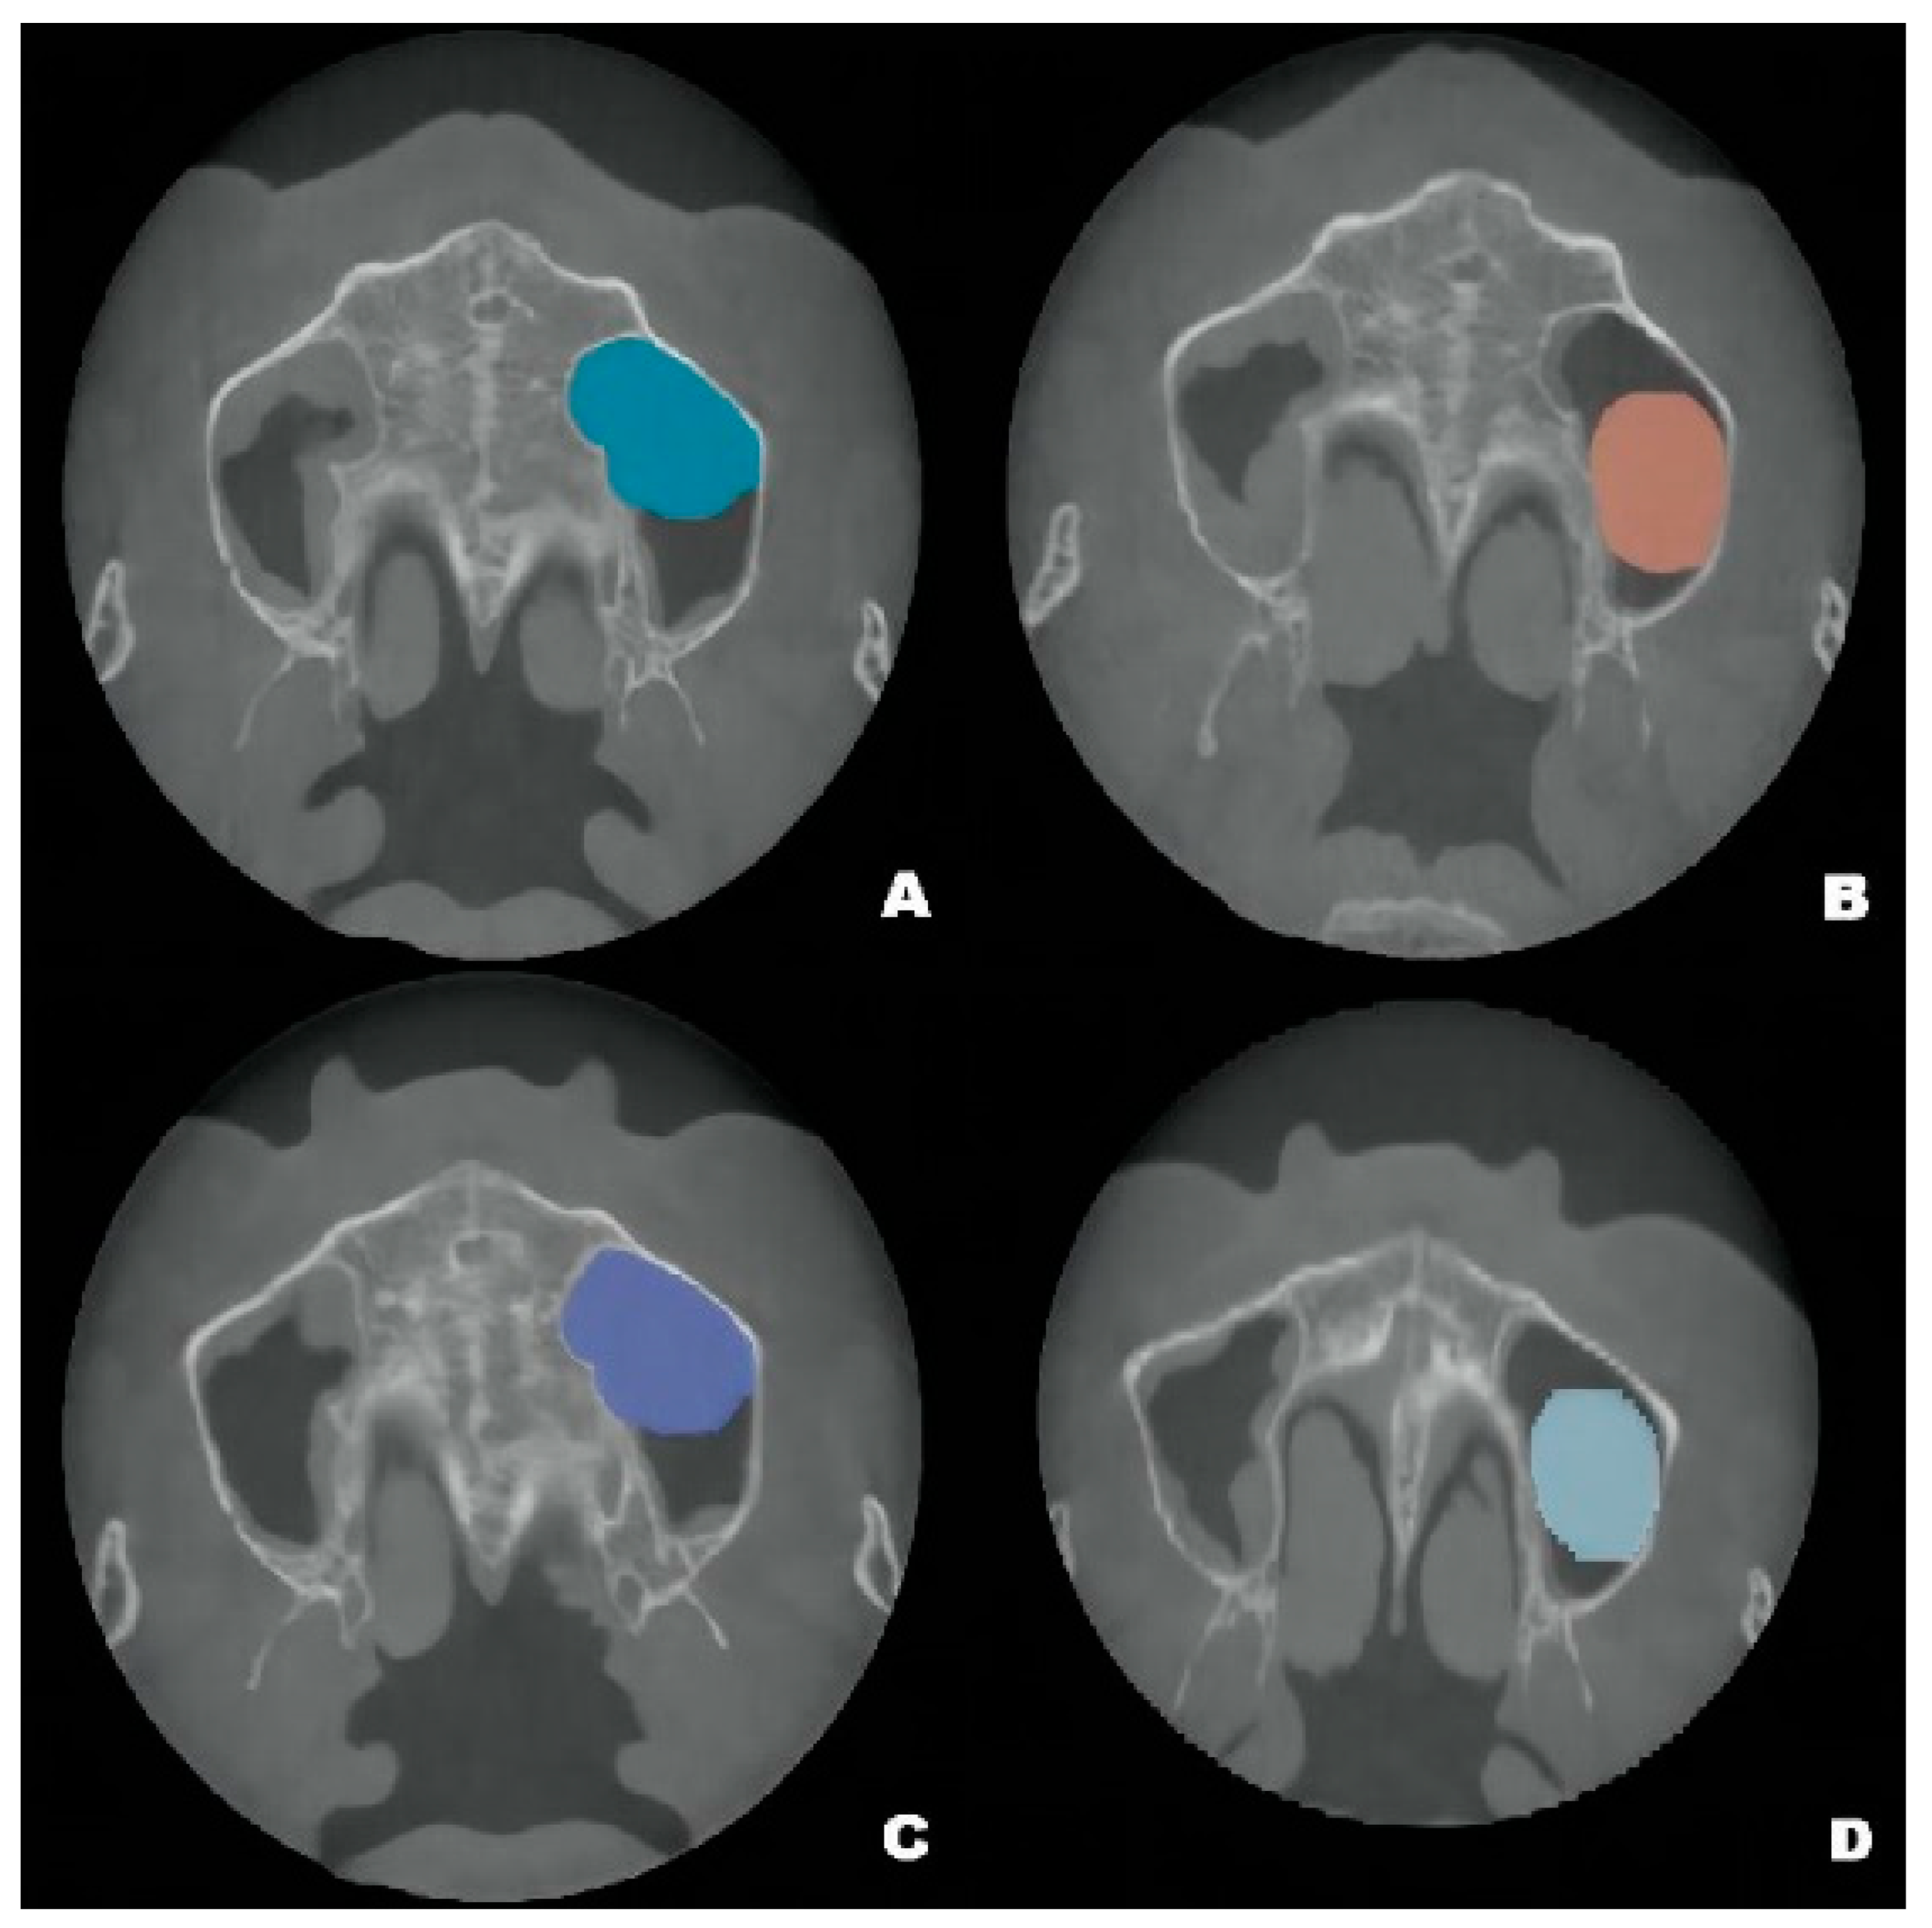

Figure 4.

Pseudocyst drift behavior: the pseudocyst had moved posterolaterally from the preoperative position (A) at 6 months after surgery (B), then returned to its original position at 12 months after surgery (C). At 22 months, the pseudocyst had remigrated to the posterolateral position (D).

Although the final crown restoration (second procedure) was planned for 6 months after the first procedure, it was delayed until 10 months because of an outbreak of COVID-19. A CBCT scan at the 6-month follow-up showed that the implants had been correctly placed in the augmented sinus, resulting in osseointegration without mobility (Figure 3B). CBCT scans at 12 months and 22 months showed stable bone levels around the implants (Figure 3C,D). The patient reported no discomfort or other complaints in relation to the implants or the maxillary sinus, and no fluid leakage was evident on the incision line during follow-up. However, a comparison of the preoperative CBCT scans with the postoperative scans conducted at 6, 12, and 22 months revealed pseudocyst drift in the left maxillary sinus (Figure 4). At 6 months after surgery, the pseudocyst had moved posterolaterally from the preoperative position near the anterior medial maxillary sinus, then returned to its original position at 12 months. However, it had remigrated to the posterolateral position at 22 months.

The pseudocyst volume was manually segmented using 3D Slicer and corrected by a professional radiologist [19]. Measurements of the maxillary sinus pseudocyst revealed that its volume decreased from 3.795 mm3 before surgery to 2.370 mm3 at 6 months post-surgery; it gradually returned to the preoperative volume at 12 months (3.439 mm3), then decreased to 2.930 mm3 at 22 months (Figure 2).

Pseudocyst drift may result from the following factors. First, the pseudocyst may not be completely immobile on the maxillary sinus floor. The pseudocyst may be entirely detached from the sinus floor, or it may be solely attached to the anterior portion of the sinus floor. In either situation, various forces, including implant insertion, airflow pressure from breathing, and postural changes during radiographic assessment could influence pseudocyst location. Second, considering the changes in volume, multiple pseudocysts may be present; the sizes of the pseudocysts may increase and decrease over time.

The apparent reduction in pseudocyst volume after implantation may have resulted from the leakage of pseudocyst fluid during implantation; however, no obvious pseudocyst fluid leakage was observed during surgery because of difficulty distinguishing such fluid from saline solution. However, follow-up imaging revealed re-enlargement and re-contraction of the pseudocyst, indicating that the changes in volume were not solely related to surgery. We suspect that changes in the secretion and absorption of fluid from a single pseudocyst contributed to these imaging findings; alternatively, multiple pseudocysts were present in our patient. If multiple pseudocysts are present, the changes in volume may represent different pseudocysts and could explain the apparent pseudocyst drift behavior mentioned above.